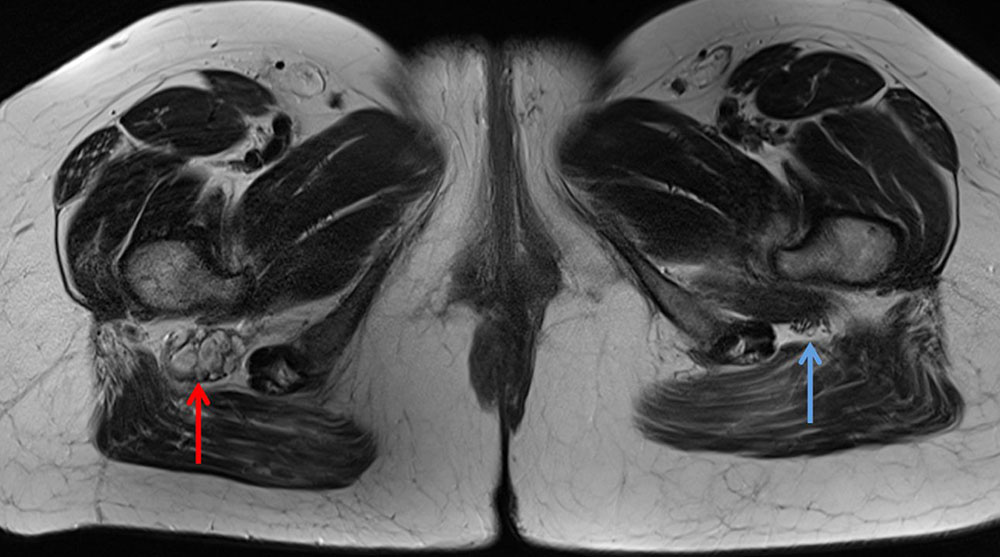

These clearly elevated D-dimer levels in patients with venous malformations, who may be otherwise quite healthy, do not occur in any other disease and are thus an important differential diagnostic component. Stagnant blood within the venous malformation results in classic fluid-fluid levels on imaging due to corpuscular blood components sinking with gravity in the absence of blood flow.

The normal organizing degradation of larger local thrombi or thrombophlebitis can lead to collagen deposition, which is palpable as a circumscribed induration over a longer period of time. If the thrombus then still cannot be completely degraded in the venous malformation, calcium deposition and increasing local, shell-like or popcorn-like calcification will occur over time. The final form is the calcified phlebolith as a round calcified lesion 1 cm in size on X-ray images of the venous malformation.